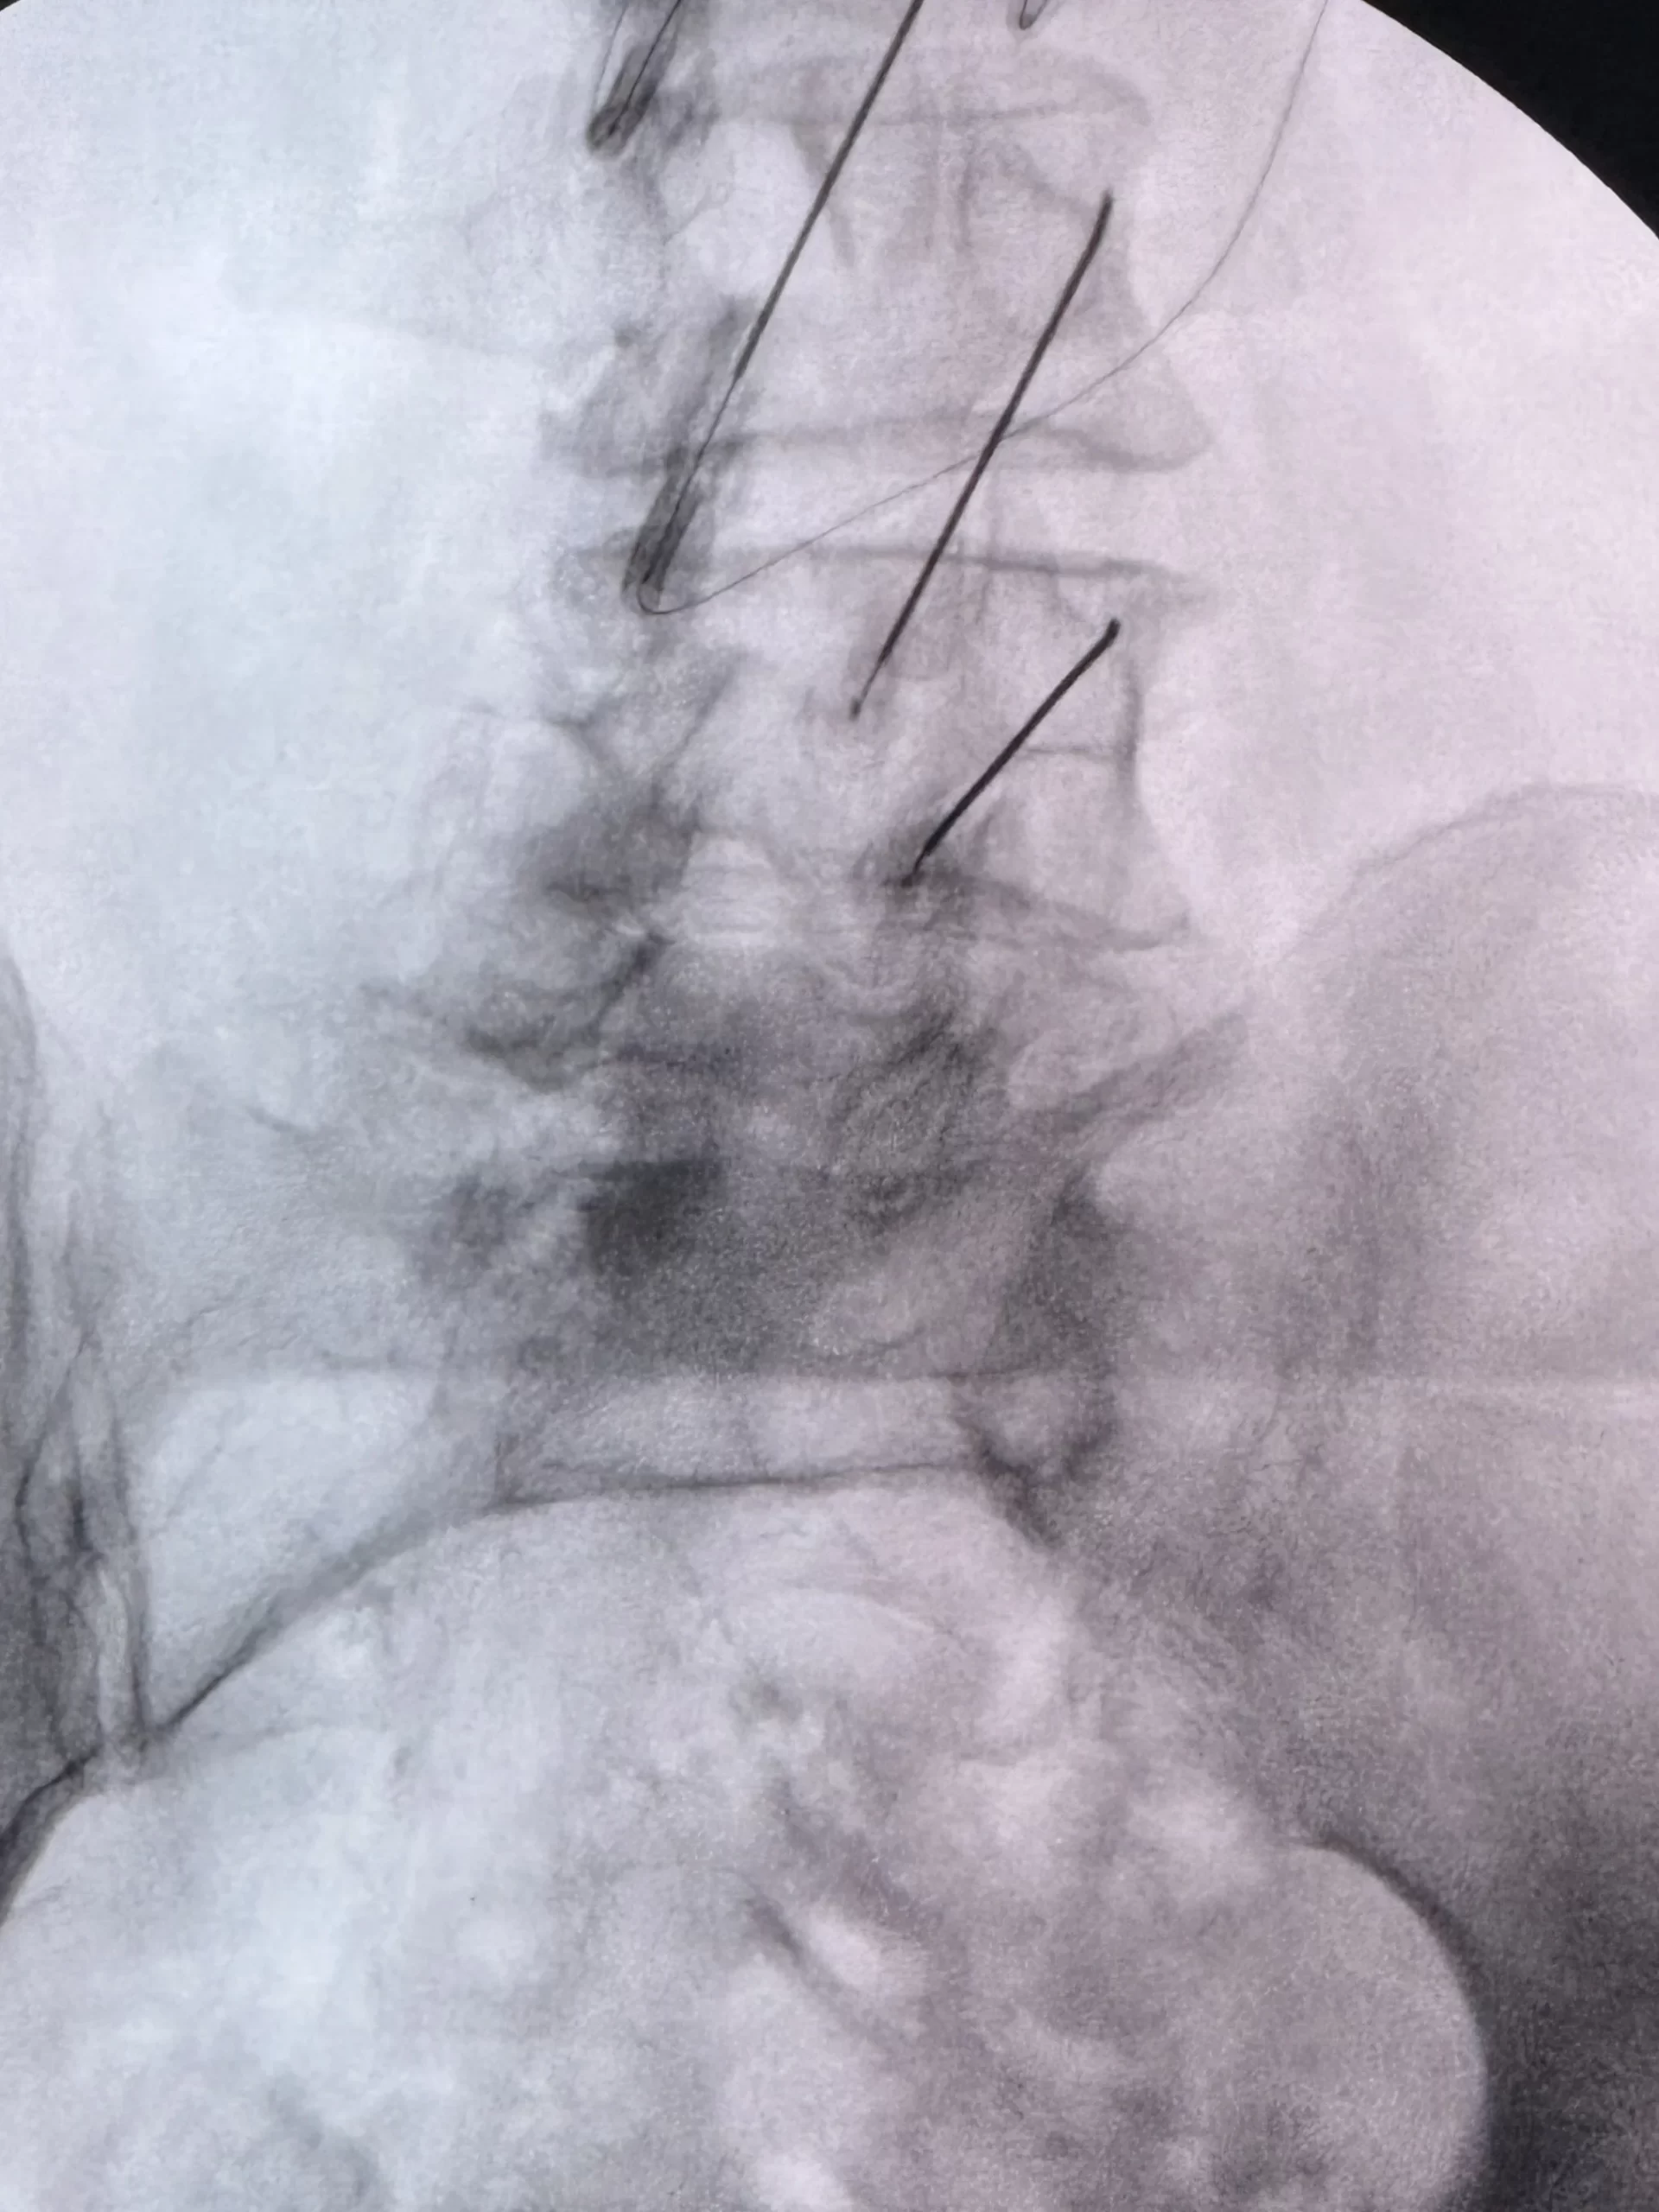

Nuestro objetivo es mejorar tu calidad de vida y acompañarte en cada paso con tratamientos mínimamente invasivos

Anestesiólogo con Subespecialidad en Algología Intervencionista con más de 10 años de experiencia en el tratamiento y alivio del dolor. Su enfoque combina profesionalismo, tecnología de vanguardia y un equipo multidisciplinario altamente capacitado para brindar atención excepcional e integral a cada paciente, mejorando su calidad de vida.